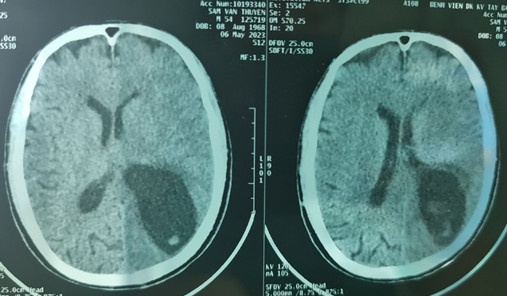

Tại đây bệnh nhân đã làm các xét nghiệm phân tìm ký sinh trùng (+), xét nghiệm Elisa chẩn đoán ấu trùng sán lợn Cysticercosis(+), chụp cắt lớp vi tính não cho thấy có nhiều ổ giảm tỷ trọng kèm phù não lớn vùng bán cầu trái.

Sau hội chẩn, các bác sĩ chẩn đoán bệnh nhân bị hội chứng tăng áp lực nội sọ do ấu trùng sán dây lợn trên hệ thần kinh, nguy cơ tử vong cao nếu không xử lý kịp thời.